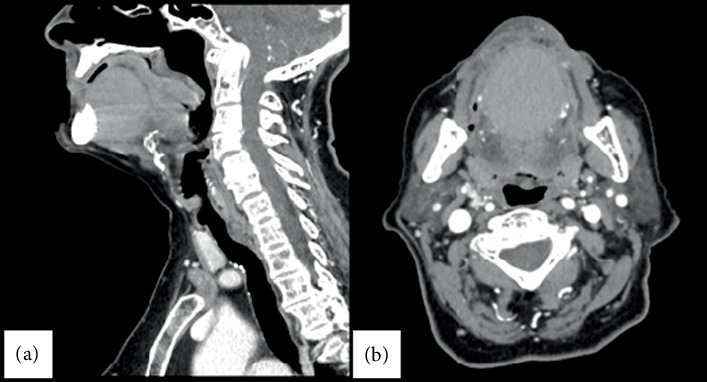

目的:本研究的目的是报告一例80岁女性患者的口腔底皮样囊肿,并讨论其临床表现、诊断方法和治疗。方法:回顾性分析特雷维吉纳大学2号院颌面外科的病例。患者有高血压病史,口腔底肿胀。临床检查后进行面部CT扫描,有或没有造影剂评估囊性病变。患者在全身麻醉下接受手术切除,并进行组织病理学分析。结果:CT扫描显示一个圆形,均匀,高密度的形成,注射造影剂后无增强。手术切除采用口内入路,组织病理学证实了皮样囊肿的诊断,上皮内衬主要为鳞状型。患者无并发症,随访9天2个月完全康复。结论:口腔皮样囊肿虽然在成人中很少见,但在口腔底肿的鉴别诊断中应予以考虑。早期诊断通过临床检查和影像学,随后手术切除,提供有效和治愈的治疗。

Aim: The aim of the study is to present a case of a dermoid cyst in the oral floor of an 80-year-old female patient and discuss its clinical presentation, diagnostic approach, and treatment. Methods: A retrospective case study was conducted at the Department of Maxillofacial Surgery, Aulss 2 Marca Trevigiana. The patient, with a medical history of hypertension, presented with a swelling in the oral floor. A clinical examination was followed by a facial CT scan with and without contrast medium to evaluate the cystic lesion. The patient underwent surgical excision under general anesthesia, with subsequent histopathological analysis. Results: The CT scan revealed a round, homogeneous, hyperdense formation with no enhancement after contrast administration. Surgical excision was performed using an intraoral approach, and histopathology confirmed the diagnosis of a dermoid cyst with an epithelial lining of predominantly squamous type. The patient experienced no complications, and follow-up at 9 days and 2 months showed complete recovery. Conclusion: A dermoid cyst of the oral cavity, though rare in adults, should be considered in the differential diagnosis of oral floor swellings. Early diagnosis through clinical examination and imaging, followed by surgical excision, provides an effective and curative treatment.